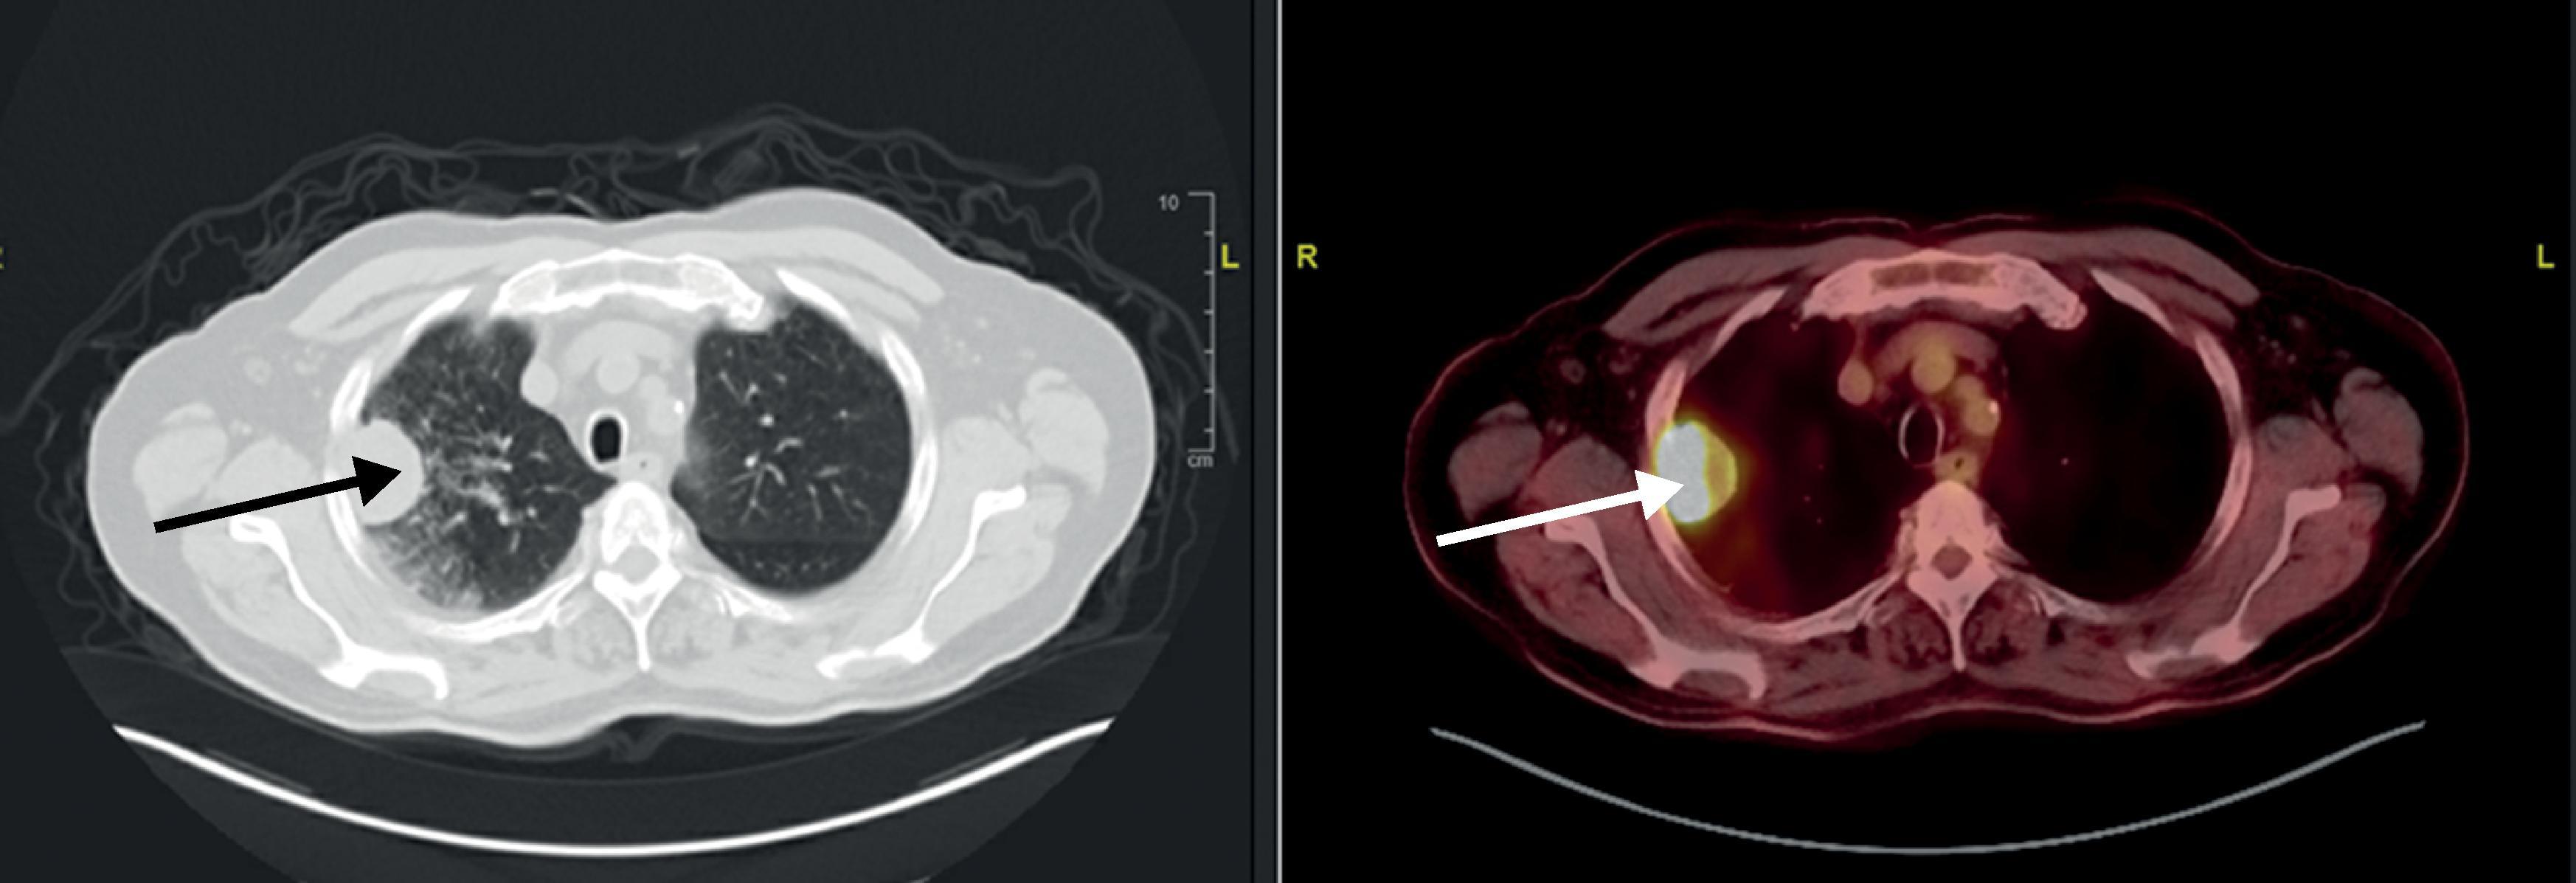

Once the decision to proceed with surgery has been made, the extent of resection and surgical approach must be considered. Lobectomy has been considered the gold standard technique for resection. The Lung Cancer Study Group reported increased locoregional recurrence rate and a trend toward decreased survival with limited resection versus lobectomy in 1995 ( Fig. 4.1 ). However, with the advent of lung cancer screening and the discovery of smaller cancers, this is being challenged, as more recent studies suggest no significant differences in recurrence rates and overall survival. The authors consider performing a sublobar resections in patients with small (<2 cm), anatomically feasible cancers with low standardized uptake value ( Fig. 4.2 ). Extended resections may be required in the setting of locally advanced disease, such as chest wall invasion ( Fig. 4.3 ) or invasion of the great vessels.

• Fig. 4.3, A CT scan of a 73 years-old male (left) with hypermetabolic 4.2 cm right upper lobe on PET scan (right). Chest wall invasion was noted, and he underwent right upper lobectomy with chest wall resection and reconstruction. Pathology was a 7-cm T3N0 pleomorphic carcinoma.